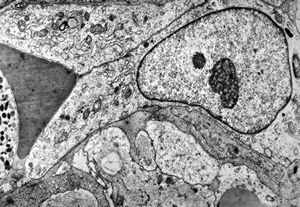

F,49y. | hemangioblastoma - brain